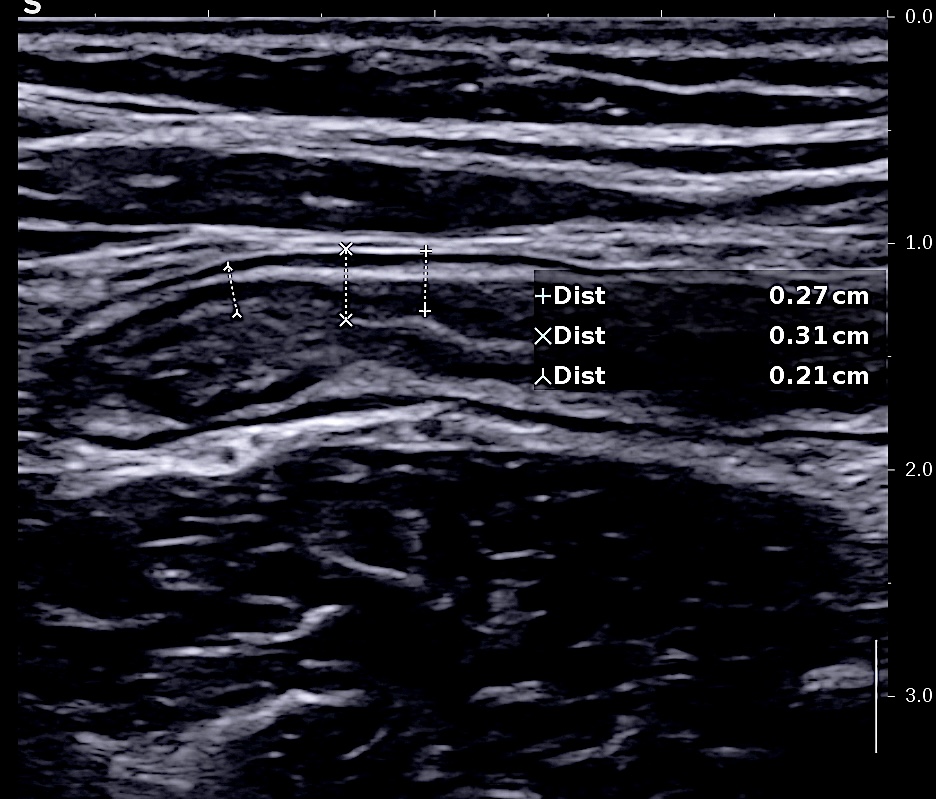

C'est l'élément le plus sensible et le plus reproductible (inter et intra observateur)

Au delà de 3 mm la paroi est épaissie.

Elle est très importante si on veut être fiable et reproductible et pouvoir suivre l'évolution de l'inflammation

L'épaississement se mesure entre la muqueuse (hypoéchogène) et la musculeuse (hypoéchogène),

Il faut faire la moyenne de plusieurs mesures (≥3) en coupe longitudinale et transversale

L'échographie est la technique radiologique qui a la meilleure résolution (millimètre)